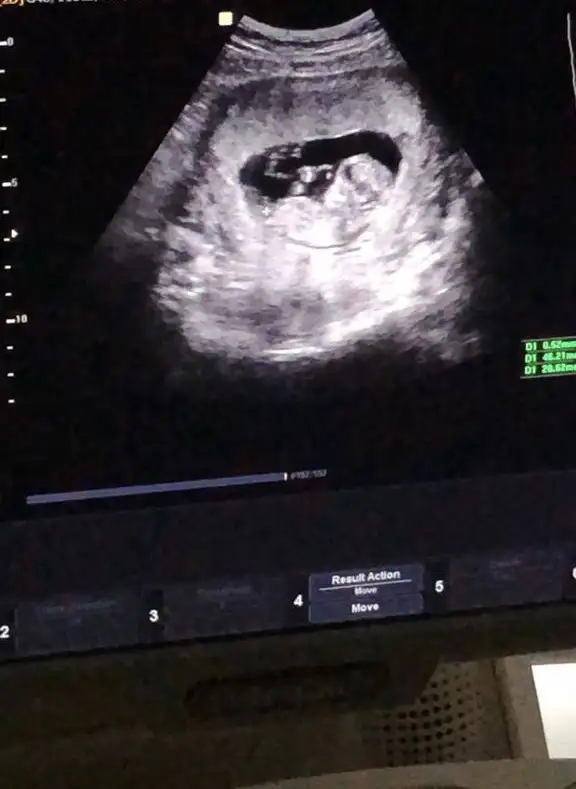

dr soylemeden siz gorun genital nub teorisi ( bebegin cinsiyeti)

Merhaba kızlar daha öncede ultrason görüntüsü paylaşmıştık fakat pek net olmadığı için yorum yapamamıştınız.Rica etsem yine bakabilir misiniz? Şimdiden teşekkürler🤗